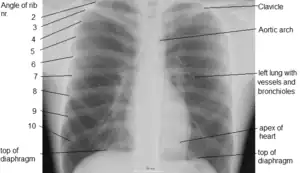

X-ray image of the chest showing the internal anatomy of the rib cage, lungs and heart as well as the inferior thoracic border–made up of the diaphragm.

An X-ray of a human chest area, with some structures labeled

The contents of the thorax include the heart and lungs (and the thymus gland); the major and minor pectoral muscles, trapezius muscles, and neck muscle; and internal structures such as the diaphragm, the esophagus, the trachea, and a part of the sternum known as the xiphoid process. Arteries and veins are also contained – (aorta, superior vena cava, inferior vena cava and the pulmonary artery); bones (the shoulder socket containing the upper part of the humerus, the scapula, sternum, thoracic portion of the spine, collarbone, and the rib cage and floating ribs).